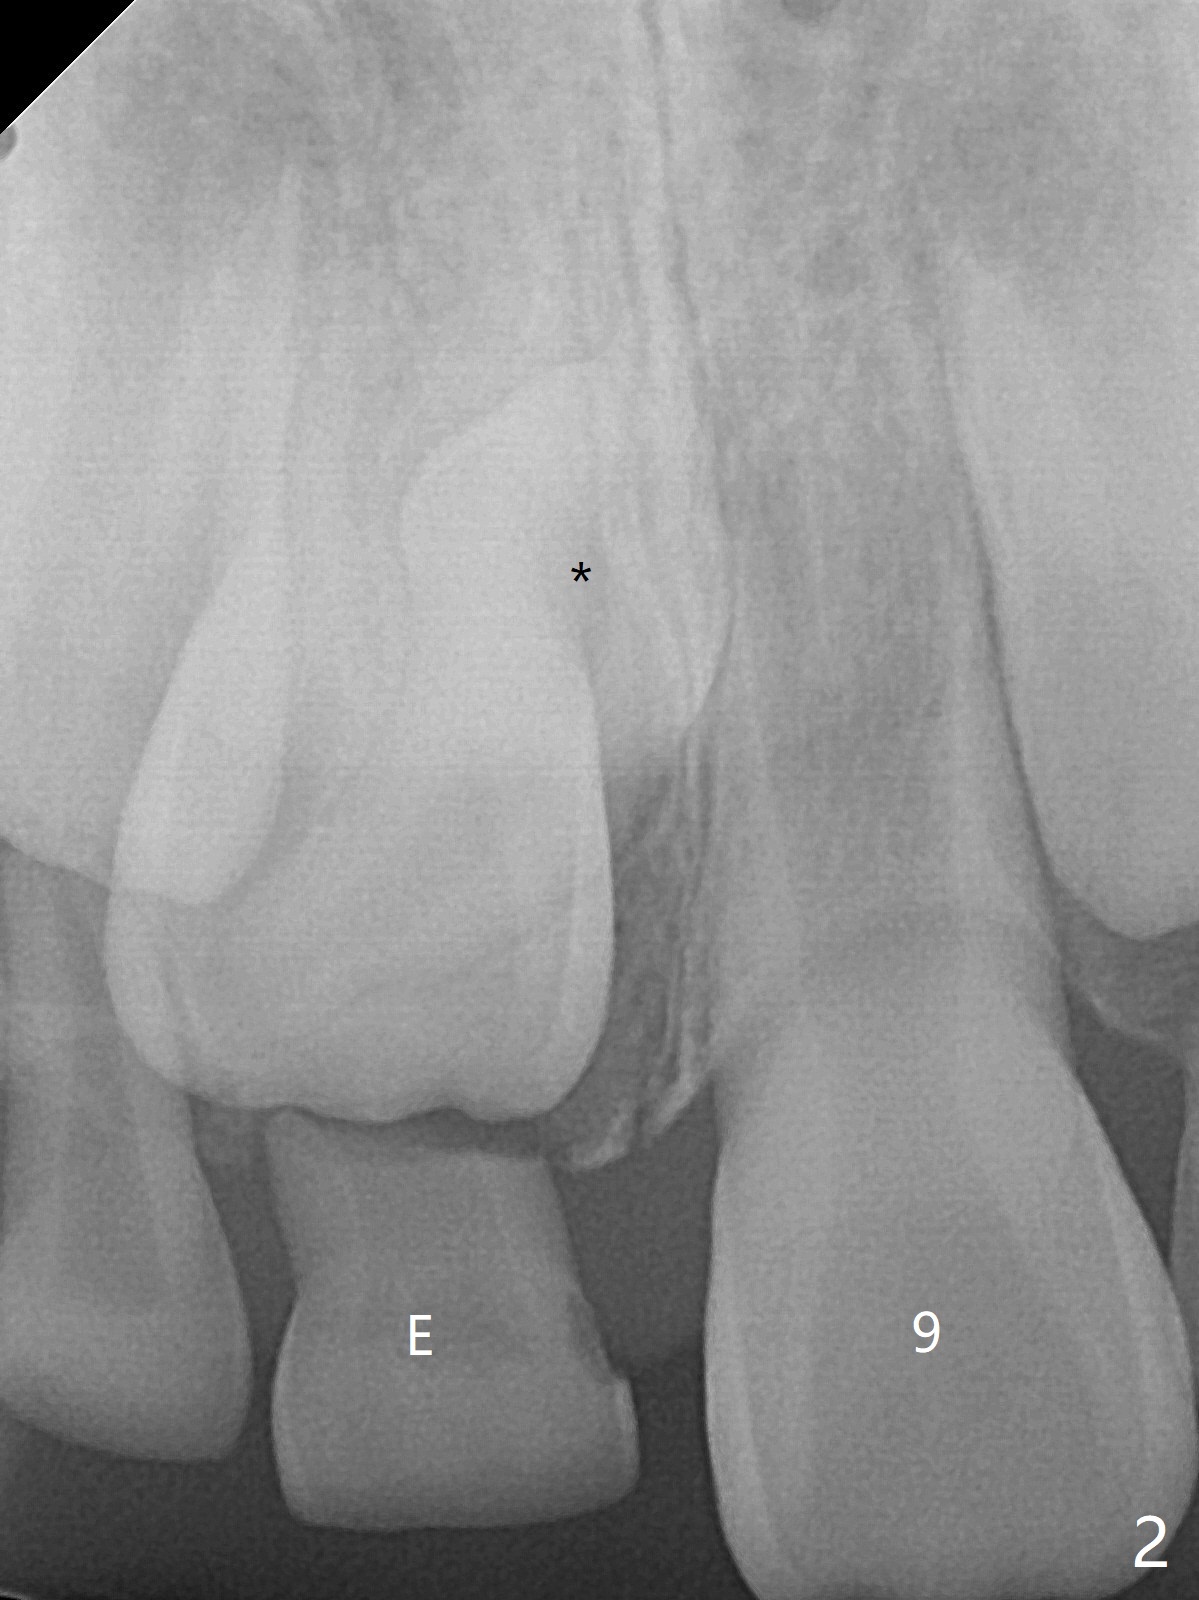

8岁男,右上乳中切牙滞留(图一,二:E),全景片,根尖片显示多生牙(图一,二:*),CT表明它位于腭侧(图三:P)。病人将今天(八岁八个月)回来拔除,腭侧牙龈缘切口应该容易暴露。